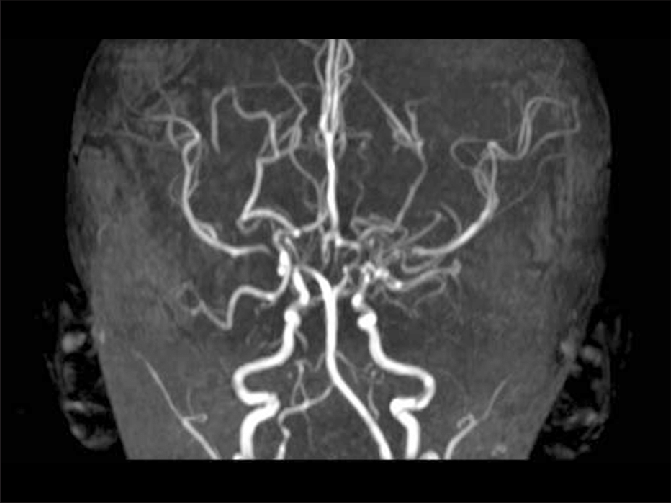

烟雾病的早期症状有哪些?烟雾病是一种少见的血管(血管)疾病,颅骨中的颈动脉堵塞或变窄,减少了流向大脑的血液。然后在大脑底部形成微小的血管,试图为大脑供血。这种情况可能...